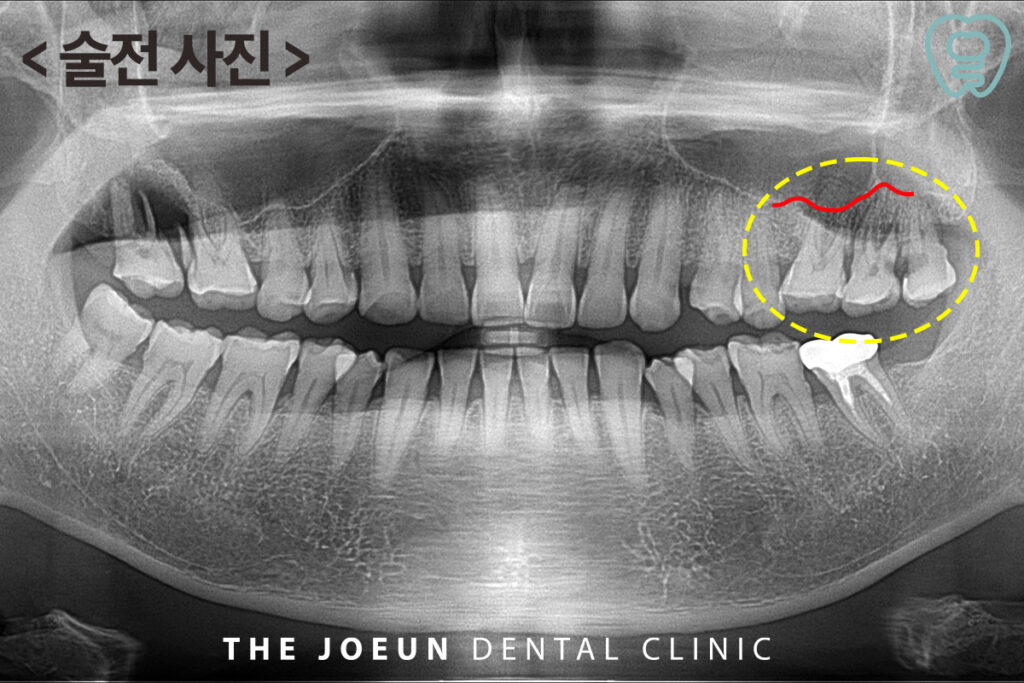

오늘은 상악동 거상술 중 치조정 접근법을 동반하여 발치 후 즉시 임플란트 수복을 3개월 안에 완성하신 케이스를 소개해 드리려고 합니다.

환자분께서는 왼쪽으로 음식을 먹을 때 음식물도 많이 끼시고 최근 들어 힘이 들어가지 않고 불편한 느낌이 드신다며 내원해 주셨습니다. 파노라마 사진 촬영을 해보니 가장 안쪽 사랑니와 인접치 사이에 심한 충치가 관찰되었고 이미 우식의 범위가 신경까지 침범하여 염증이 생겨 있었으므로 두번째 큰 어금니와 사랑니를 발치하고 어금니 부위는 임플란트 식립이 필요한 상황이었습니다. 따라서 치료 과정을 충분히 설명드린 후 계획을 수립하였습니다.